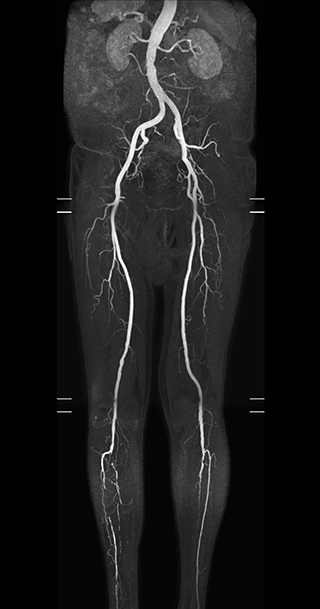

Subtractionless MRA run-off studies with exceptional spatial and temporal resolution

“In our peripheral MRA run-off studies with Ambition we realize key benefits, including outstanding image quality and significantly reduced breath-hold and scan times, which not only benefit the patient, but also provide the opportunity to add sequences that could aid in diagnosis,” Dr. Peña says.

“Before we had Ingenia Ambition, our CE-MRA run-off studies would first acquire a dynamic pre-contrast scan with 20-25-second breath-holds, then inject the contrast, do another acquisition and then subtract the two,” says Avila. “Now, mDIXON XD allows us to complete the study in just one single pass – without need for a pre-exam – which eliminates subtraction artifacts and almost halves the scan time. In addition, mDIXON provides much better background suppression, which really improves vesselto-background contrast. And, thanks to Compressed SENSE, the single breath-hold is not long and we improve image resolution.”

MRA run-off study with mDIXON

The subtractionless peripheral MR angiography shows improved vessel-to-background contrast and high resolution. Ingenia Ambition 1.5T.

Station

Ingenia Ambition

Pelvis

Voxels 1.3 x 1.3 x 3.2 mm, FOV 430 mm, 125 slices

Upper legs

Lower legs

Voxels 1.0 x 0.82 x 2.0 mm, FOV 430 mm, 125 slices